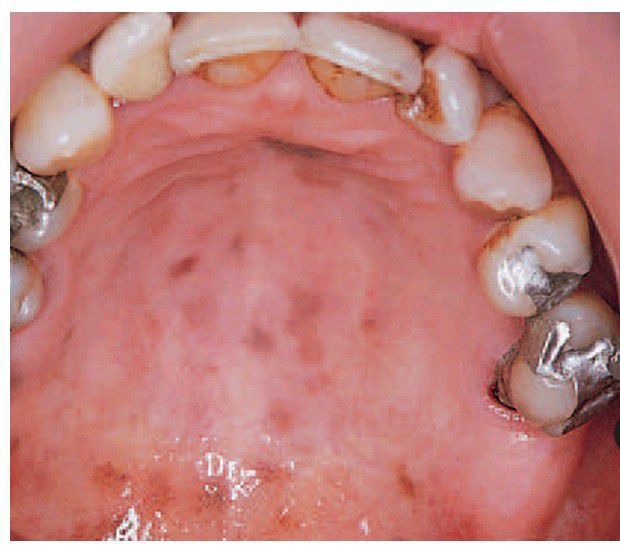

Peutz–Jehgers syndrome.

There are multiple fl at, pigmented patches on the palate. Those on the lips are most characteristic but fade with age.